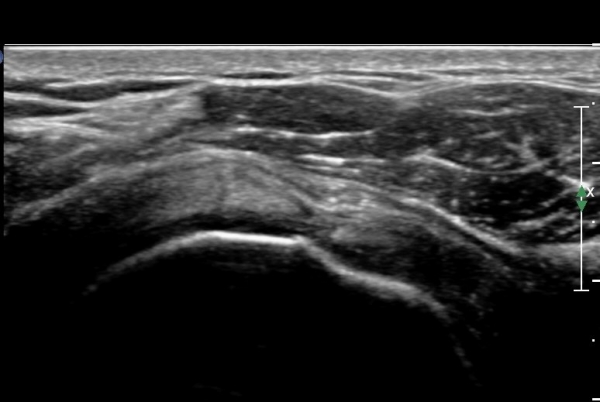

ȸÀü±Ù°³°£°Ý(rotator cuff interval)  Ⱦ´Ü¸é°Ë»ç¿¡¼­ ±¹»ó°Ç ³»ÃøÀÇ °Ç ¶Ñ²²°¡ ¾ã¾ÆÁø °ÍÀ¸·Î

º¸¿© ±Ø»ó°Ç ³»Ãø ºÎºÐÆÄ¿©¸ª ¾Ï½ÃÇÔ(»çÁø 3, ).